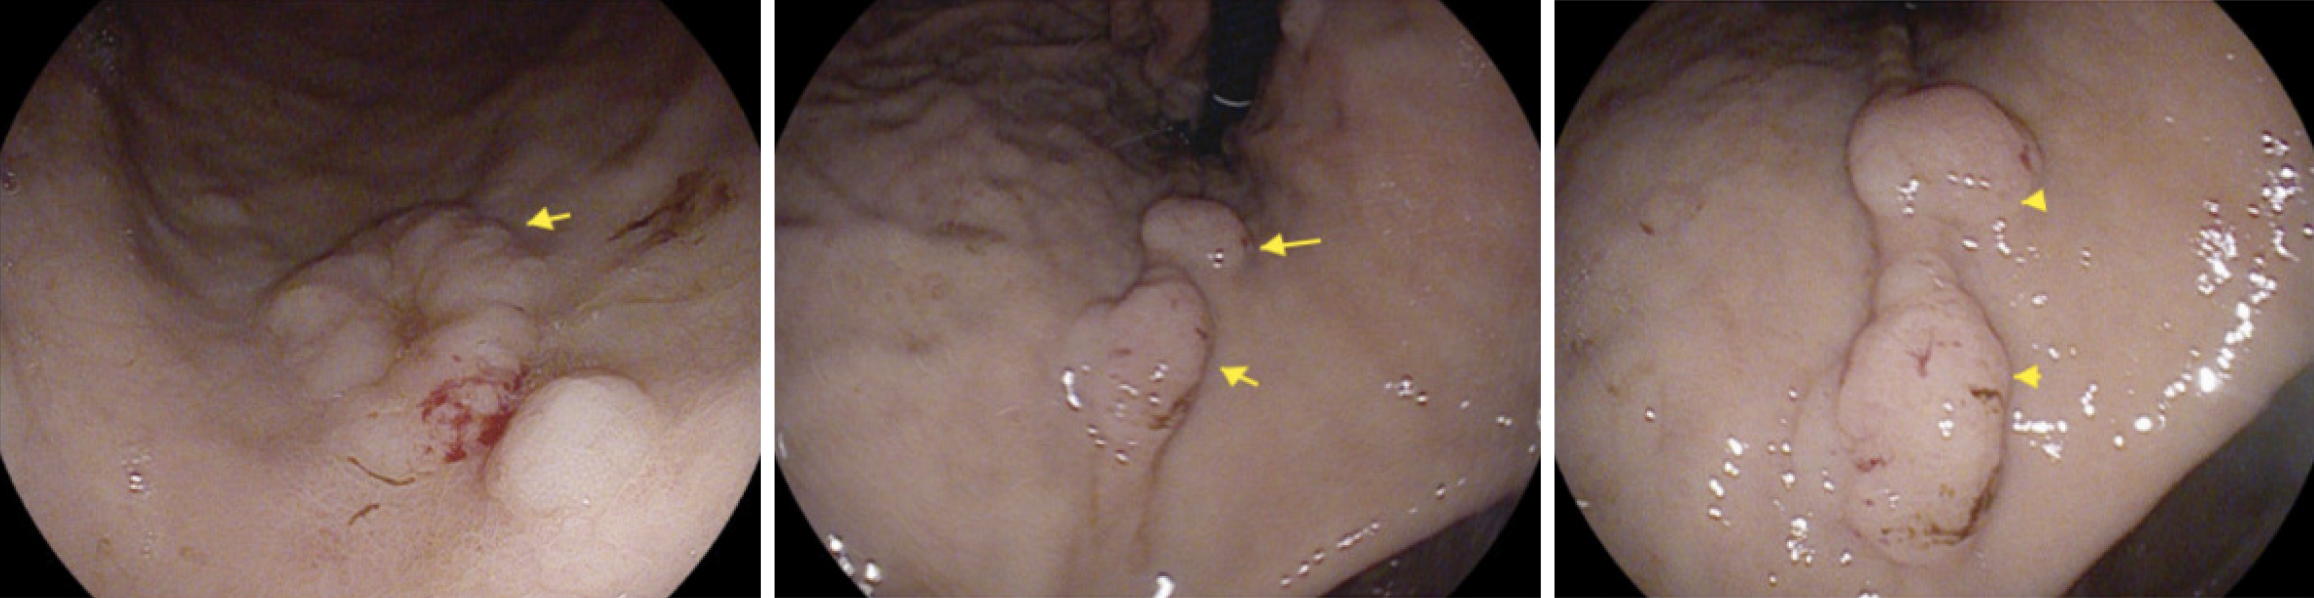

PET scan revealed disseminated, mixed, predominantly lytic bone metastases throughout the axial and appendicular skeletons, including throughout the spine, pelvis, bilateral mid to proximal humeri and femora, bilateral ribs, sternum and bilateral scapulae. There was no definite fluorodeoxyglucose-avid primary neoplasm, particularly in the lung. There was non-specific mild to moderate heterogeneous uptake in the stomach, most intensely in the proximal stomach along the greater curvature, and distal stomach along the lesser curvature and pylorus (Figure 1). There was no significant focal fluorodeoxyglucose uptake seen elsewhere to suggest other metastatic disease. Following this PET result, the patient underwent a gastroscopy with gastric nodule biopsies to further investigate the malignant process. Multiple 10-20 mm semi-sessile polyps were noted in the gastric fundus, antrum, greater and lesser curvature and the incisura (Figure 2). There were no other overt lesions identified.